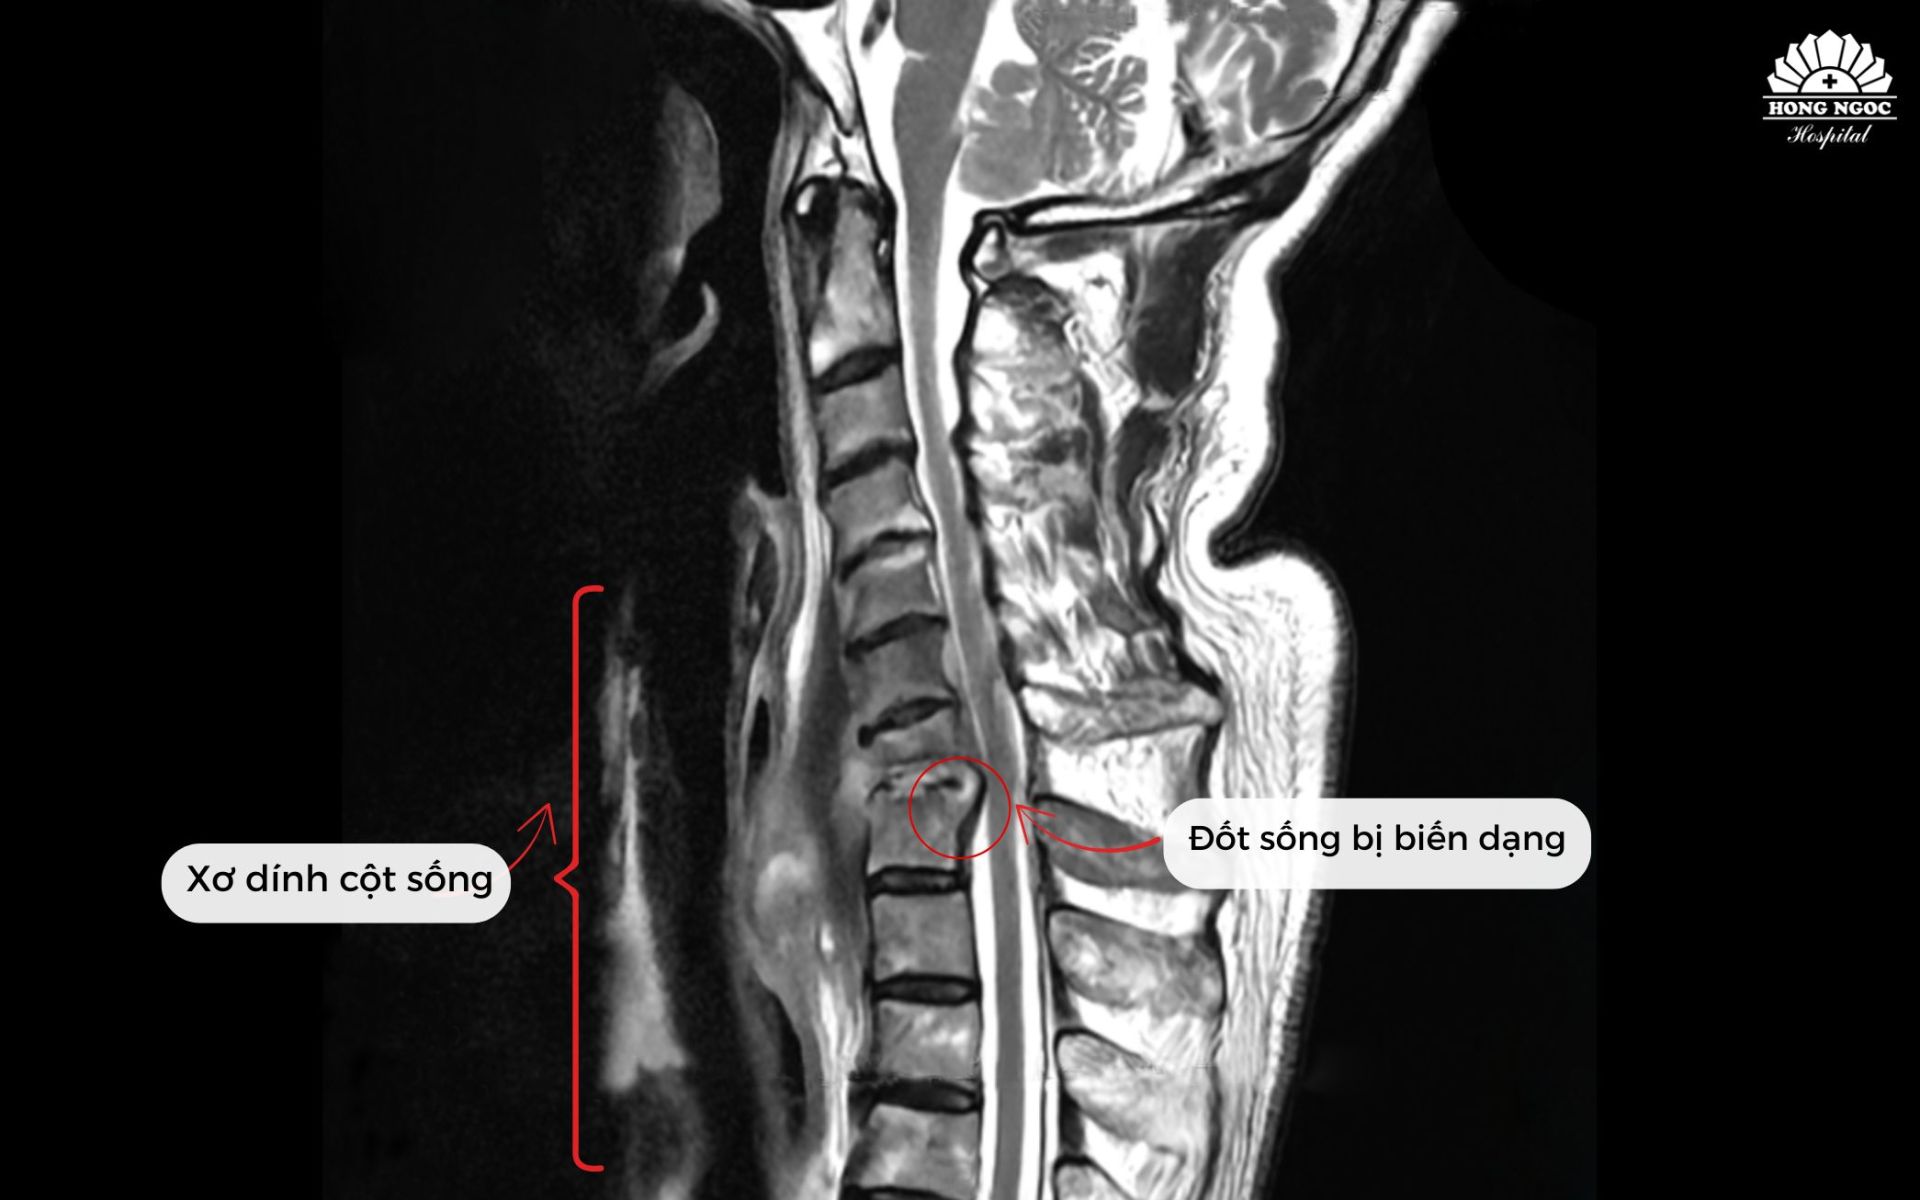

Không thể xoay ngửa cổ vì bệnh hiếm, giáo sư người Nhật sang Việt Nam phẫu thuật thành công

BVĐK Hồng Ngọc đã chẩn đoán và phẫu thuật thành công cho Giáo sư người Nhật Bản mắc bệnh lý nhiễm trùng cột sống cổ hiếm gặp, gây biến dạng đốt sống, khiến cổ không thể xoay hoặc ngửa. Sau phẫu thuật kết hợp điều trị nội khoa, bệnh nhân phục hồi tốt, cổ vận động linh hoạt.